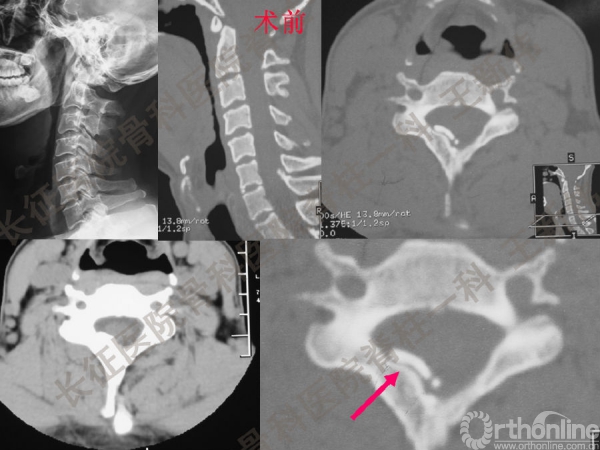

王新伟:颈椎后路通道下手术病例报告及文献回顾

颈椎后路通道下手术有哪些?颈椎后路通道下手术能做哪些事?颈椎后路通道下手术有哪些优势?长征医院骨科医院脊柱一科王新伟副教授通过临床病例报告及文献回顾,给出了他的答案——